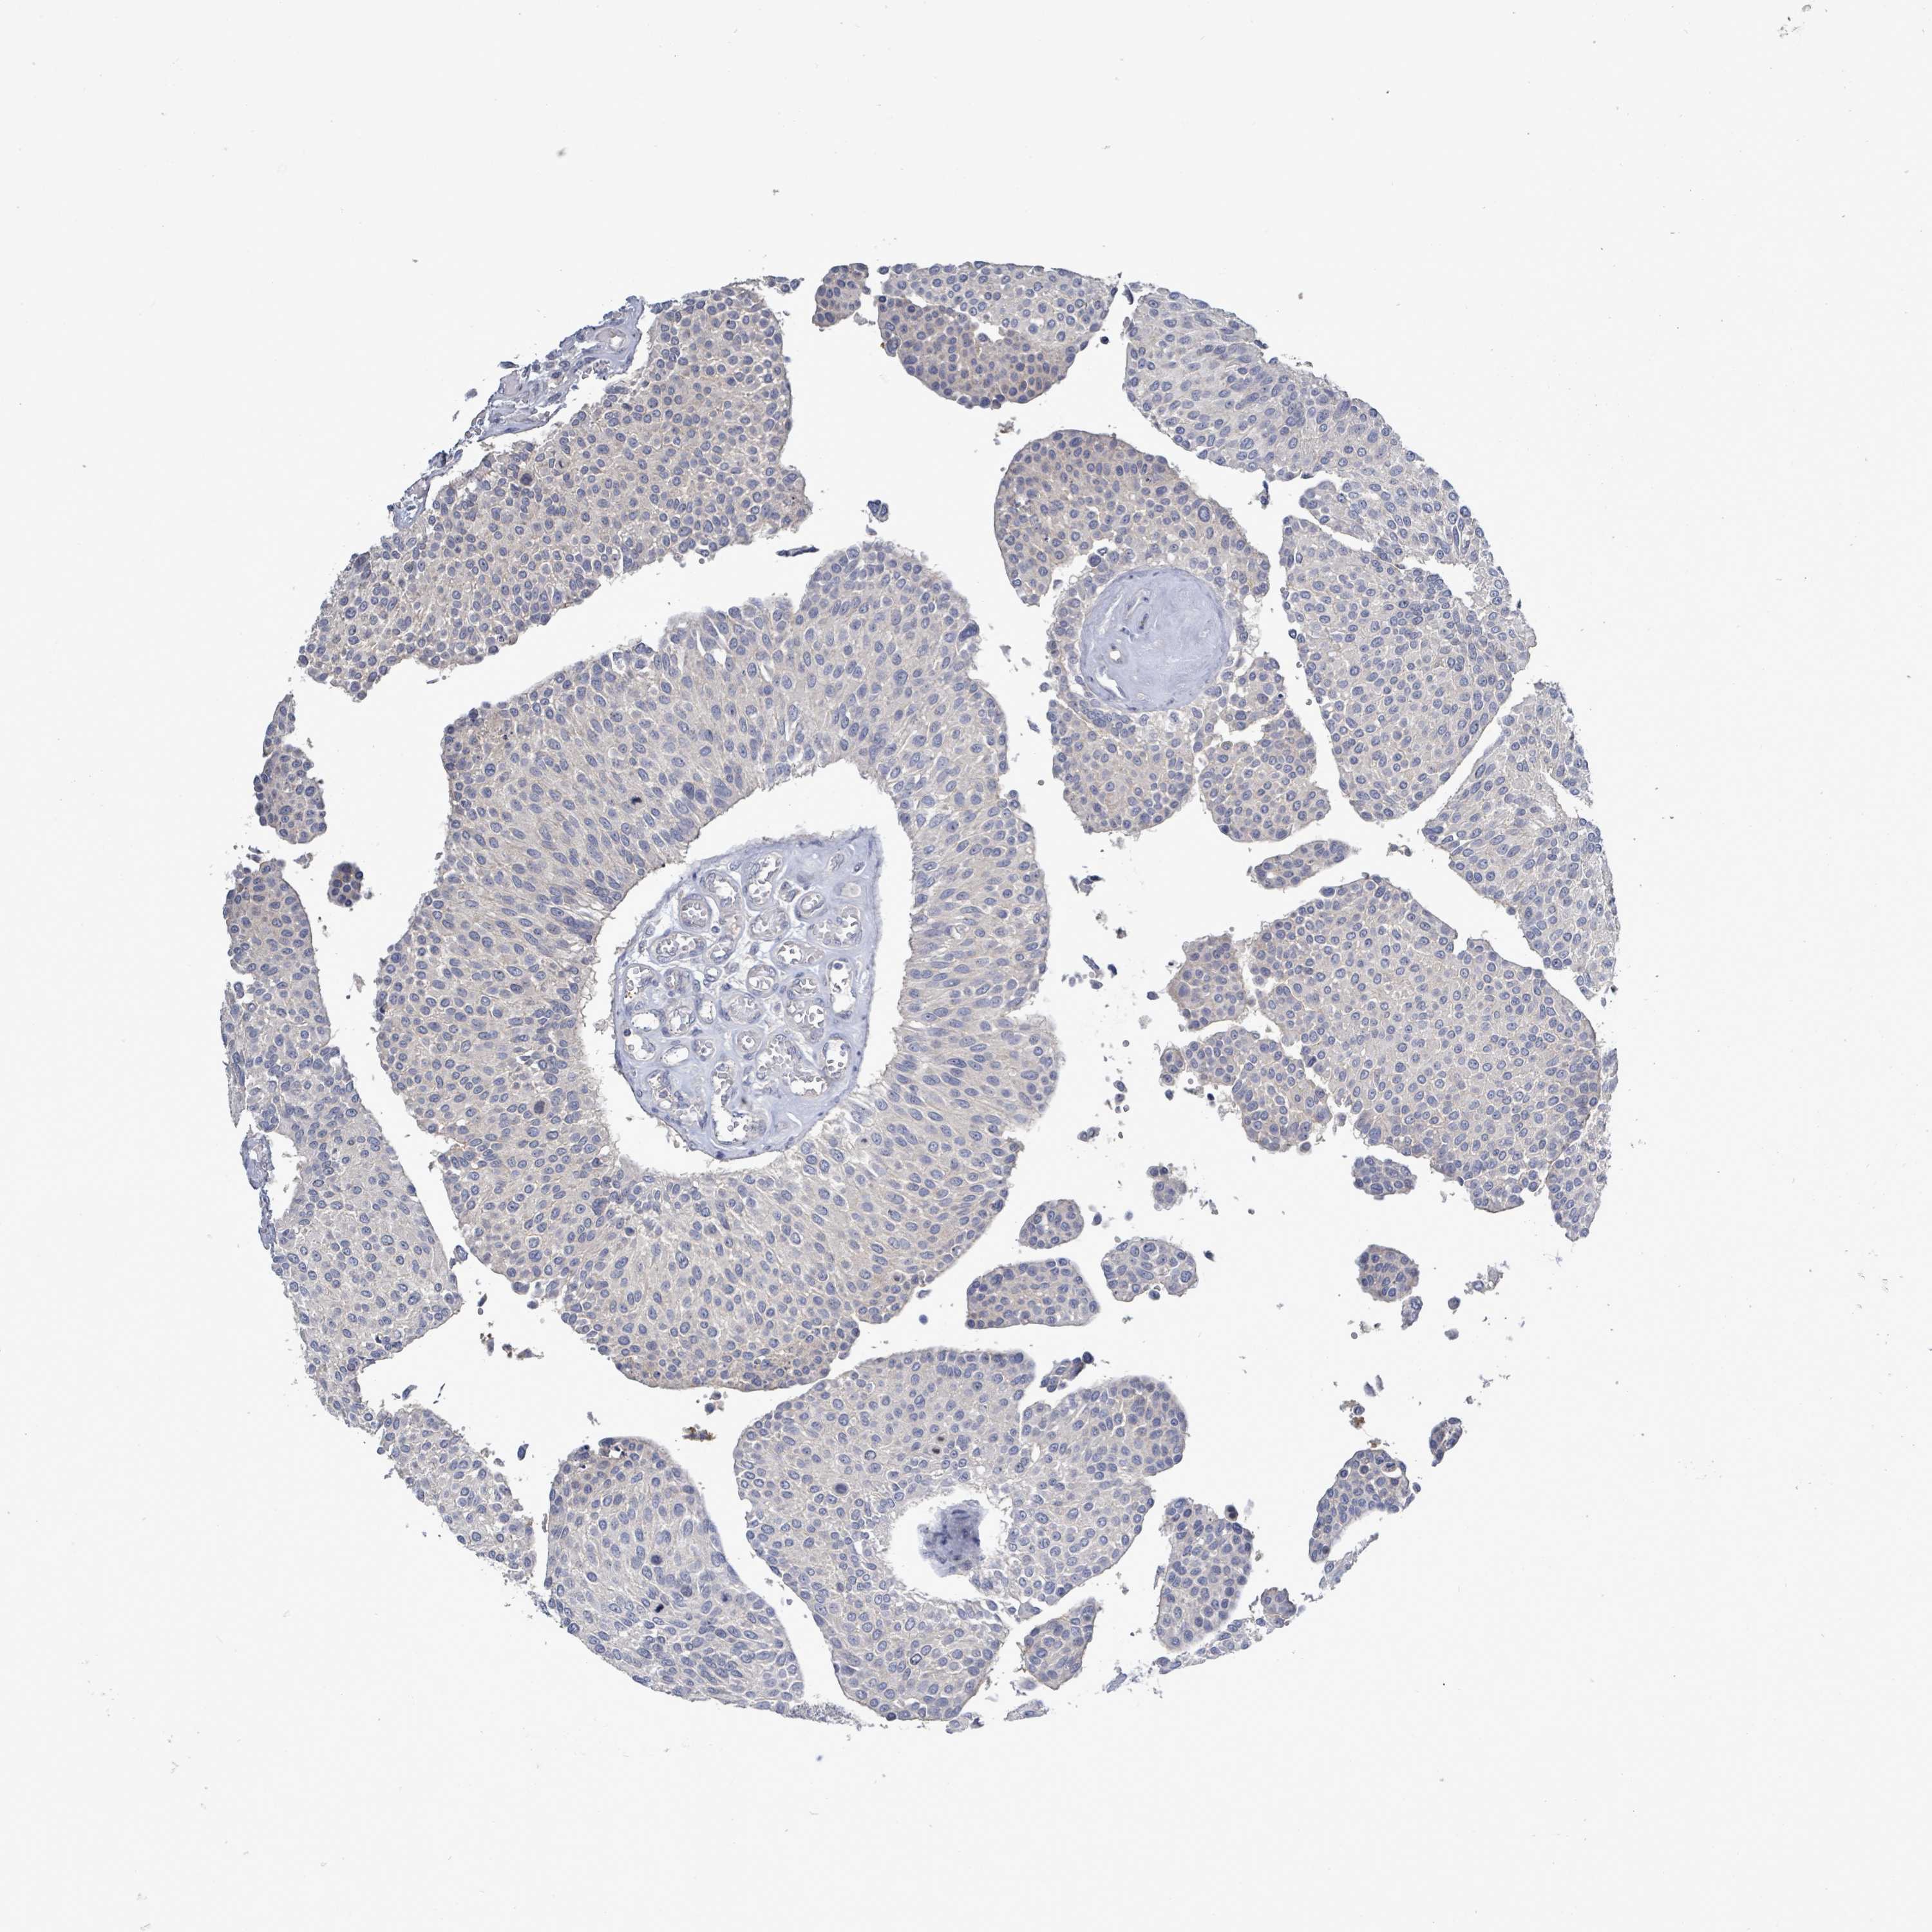

UROTHELIAL CANCER - Protein expressioni

A mouse-over function shows sample information and annotation data. Click on an image to view it in a full screen mode. Samples can be filtered based on level of antibody staining by selecting one or several of the following categories: high, medium, low and not detected. The assay and annotation is described here.

Note that samples used for immunohistochemistry by the Human Protein Atlas do not correspond to samples in the TCGA dataset.

Antibody stainingi

Antibody staining in the annotated cell types in the current human tissue is reported as not detected, low, medium, or high, based on conventional immunohistochemistry profiling in selected tissues. This score is based on the combination of the staining intensity and fraction of stained cells.

Each image is clickable and will lead to virtual microscopy that enables deeper exploration of all samples and also displays staining intensity scores, fraction scores and subcellular localization as well as patient and tissue information for each sample.

HPA049830

CAB002015

CAB080330

CAB080331

CAB080332

Urothelial carcinoma, High grade

Urothelial carcinoma, NOS

Urothelial carcinoma, Low grade

Adenocarcinoma, NOS